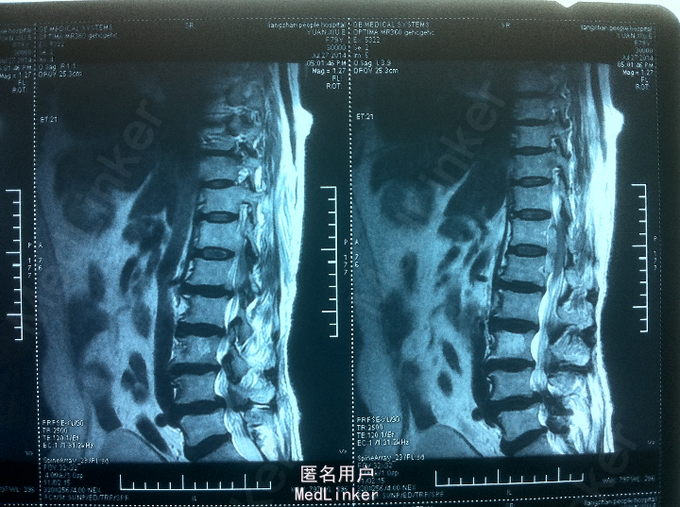

双下肢麻木、无力1天 患者老年女性,既往高血病史; 患者1天前无明显诱因起身时出现双下肢麻木,并加重,15分钟后出现双下肢无力,活动受,不能自行行走,无颈部疼痛及双上肢放射性疼痛、麻木、无力,无发热,寒战。

查体:腰部叩痛,双下肢感觉减退,双下肢肌力2-3级,双侧膝跟腱反射未引出,肌张力减弱,巴氏征未引出。 CT:腰椎硬膜外血肿可考虑 MR:腰椎硬膜外血肿

诊断:自发性腰椎硬膜外血肿 患者入院后给予甘露醇、甲泼尼龙、甲钴胺、神经节苷脂等药物,第二天,双下肢麻木较前减轻,双下肢肌力3-4级,与患者及家属沟通后,患者家属拒绝手术减压血肿清除,继续给予消肿、营养神经药物治疗,入院第5天,患者双下肢麻木明显消失,双下肢肌力4-5级,好转出院。